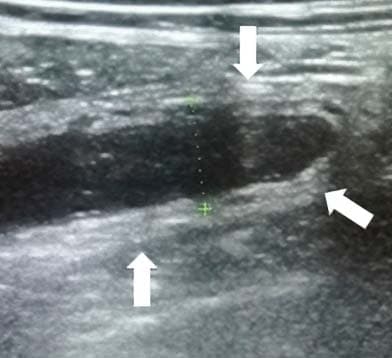

Из протокола УЗИ: «В правой подвздошной области визуализируется слепо заканчивающийся, не перистальтирующий участок кишки 7 мм в диаметре,

наполненный жидкостью, болезненный при компрессии датчиком» (см. рис. 7).

Рисунок 7. Картина УЗИ при флегмонозном аппендиците.

Рисунок 8. Хирургически удаленный аппендикс при флегмонозном аппендиците.Из протокола операции: «Червеобразный отросток увеличен, гиперемирован, инъецирован сосудами, дистально отечен, напряжен». Диагноз после операции: флегмонозный аппендицит (см. рис. 8).